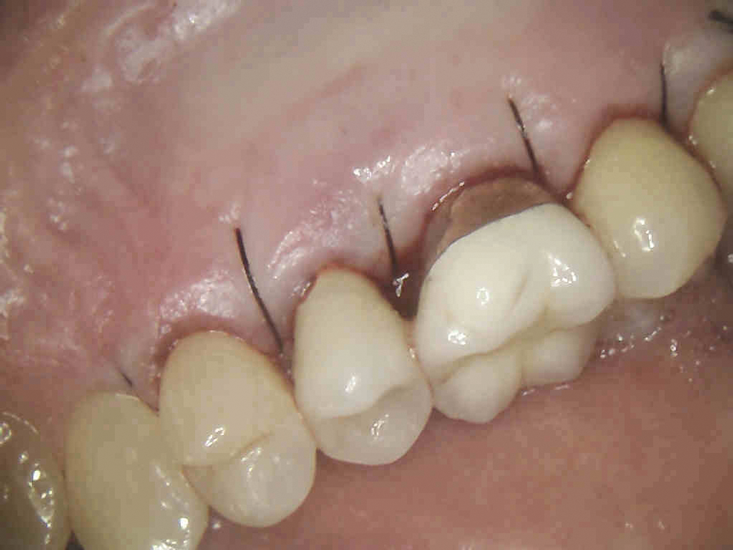

(6.) Immediate postoperative view after the flap was sutured into place (Photography courtesy of Stephen Fucini, DMD).

Figure 6